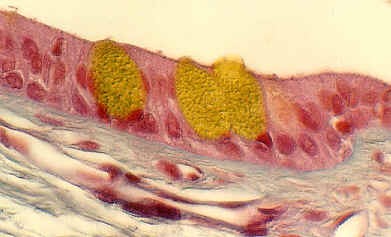

Below is another view of a large (excretory) duct of a salivary gland showing the mucin in Goblet cells after a special stain. What might be the advantages of an epithelium that has a basal cuboidal cell layer and an apical columnar cell layer?